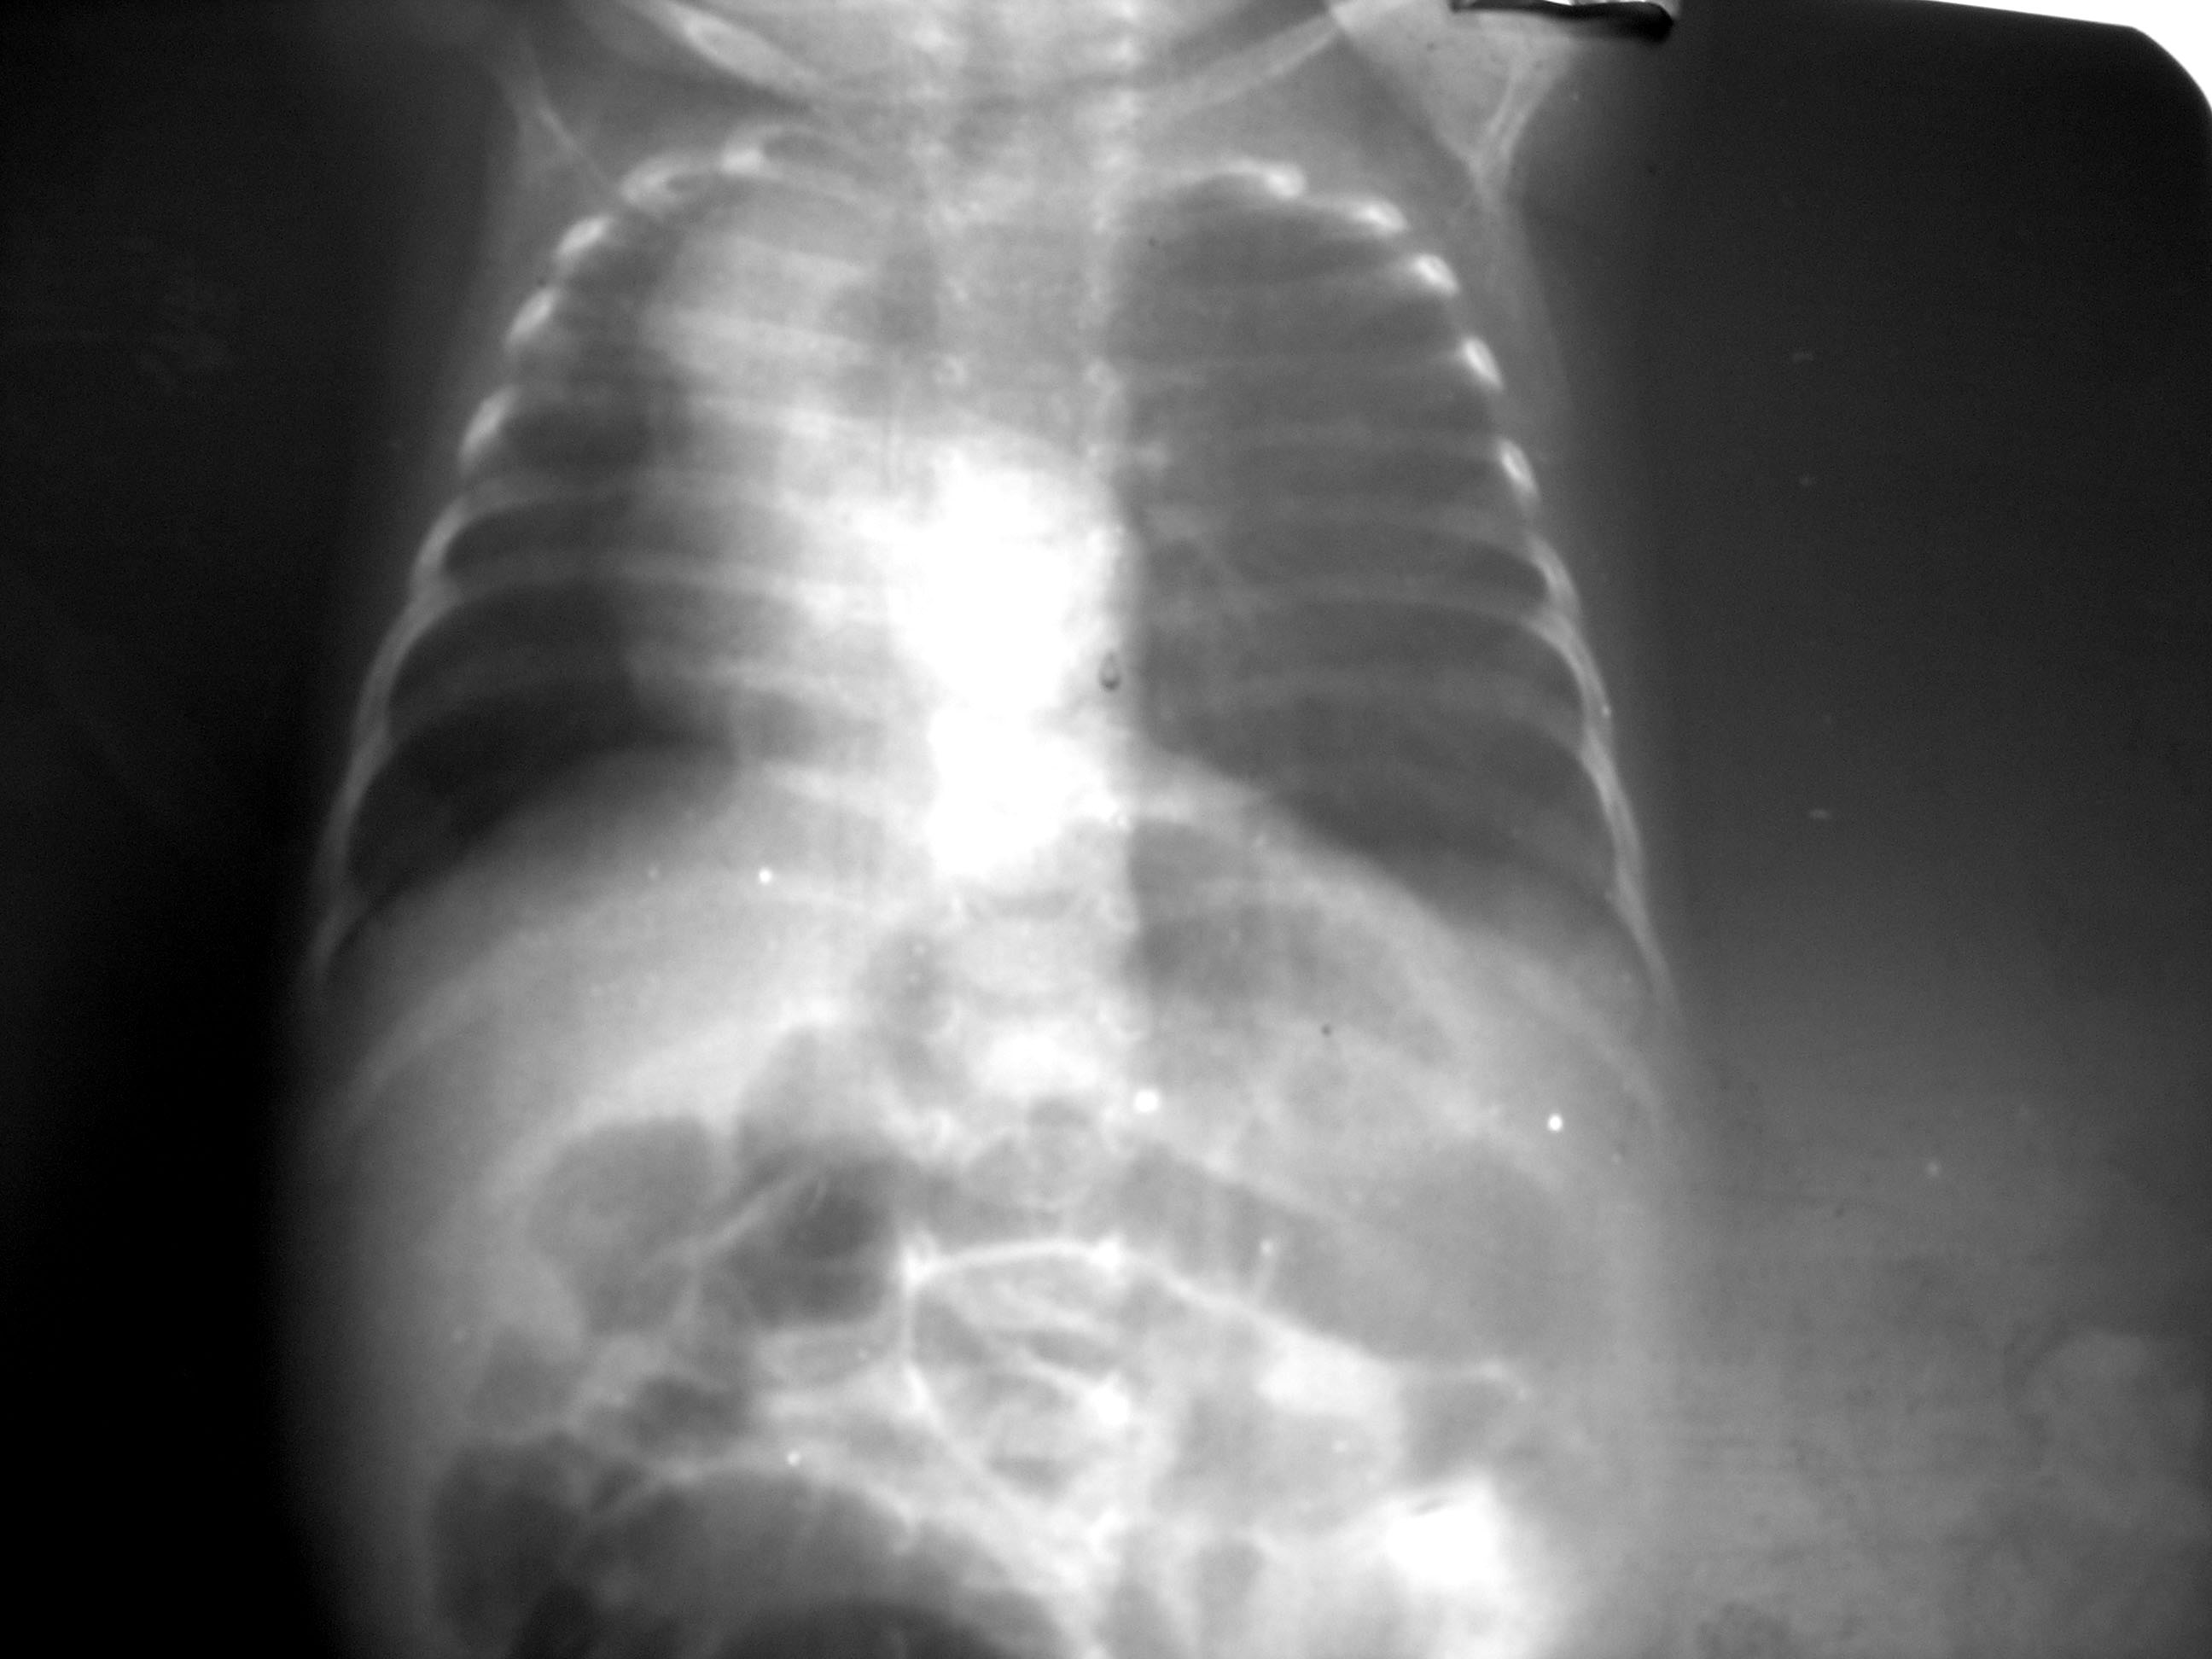

Congenital Lobar Emphysema Chest X Ray . Congenital lobar overinflation may be first diagnosed at antenatal imaging or on chest radiographs obtained in a neonate. Congenital lobar emphysema (cle) is the overinflation of one or more lung lobes, present from birth with a lung histologically normal. Initial frontal radiograph at birth demonstrate a hazy opacity occupying left upper lobe with mass effect and shifting of mediastinal structures to the right. Congenital lung anomalies, including congenital lobar emphysema, should be considered differential diagnoses.

Congenital lobar emphysema (cle) is the overinflation of one or more lung lobes, present from birth with a lung histologically normal. Congenital lobar overinflation may be first diagnosed at antenatal imaging or on chest radiographs obtained in a neonate. Initial frontal radiograph at birth demonstrate a hazy opacity occupying left upper lobe with mass effect and shifting of mediastinal structures to the right. Congenital lung anomalies, including congenital lobar emphysema, should be considered differential diagnoses.